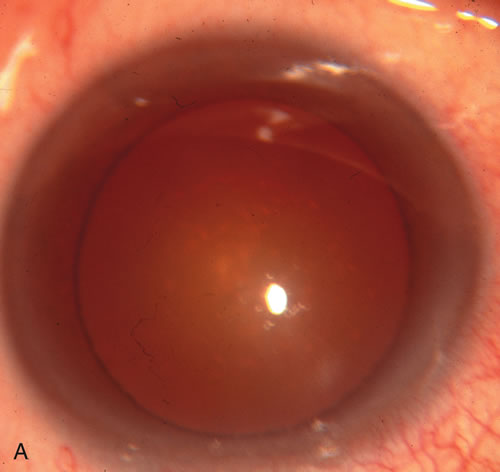

Fig. 1. The anatomic advantage of small incision cataract surgery for the glaucoma patient. A. Long-term bleb function with a large cataract incision is difficult to achieve with either ECCE-trabeculectomy or trabeculectomy followed later by ECCE. This bleb failed to form sufficiently when combined with large incision ECCE. The inflammation, bleeding, and long-term wound healing with stimulation of fibroblasts associated with this technique are more likely to cause bleb failure. In addition, the increased iris manipulation necessary to deliver the nucleus and subsequent iris repair adds to the long-term breakdown of the blood aqueous barrier. B and C. Two-site phacotrabeculectomy has the advantage of small incision cataract surgery combined with separate site trabeculectomy. The incision size is one third the size of the standard ECCE. The inflammation is less severe, and cataract wound healing is confined to the temporal area. Visual rehabilitation with phacoemulsification and foldable IOL is much faster. Phacoemulsification allows successful lens extraction even in the unfriendly environment of a smaller pupil compared with ECCE. The trabeculectomy is performed in an entirely different site, well away from the wound healing associated with temporal phacoemulsification. The likelihood of this filter functioning long-term is greater than with ECCE-trabeculectomy. D. The surgeon also has the option of single-site phacotrabeculectomy with foldable IOL. Both the lens extraction and trabeculectomy are performed through one small 3.5-mm limbal incision.

Fig. 3. Partial bleb failure following clear corneal phacoemulsification with foldable IOL. A. Preoperative bleb appearance prior to temporal lens extraction. Preoperative IOP was 12 mm Hg on no antiglaucoma medications. Time from 5-FU trabeculectomy surgery to lens extraction was one year. B. Bleb appearance 2 months after clear corneal cataract surgery with topical anesthesia. Following lens extraction, increased vascularity was noted along with decreased size of the filtering bleb. IOP increased to 20 mm Hg as early as 2 weeks after surgery, necessitating topical antiglaucoma therapy. C. High magnification view of bleb before lens extraction demonstrates diffuse pale bleb. D. High magnification view of bleb 2 months after surgery. There are vessels surrounding the nasal side of the bleb and the overall bleb size is smaller.